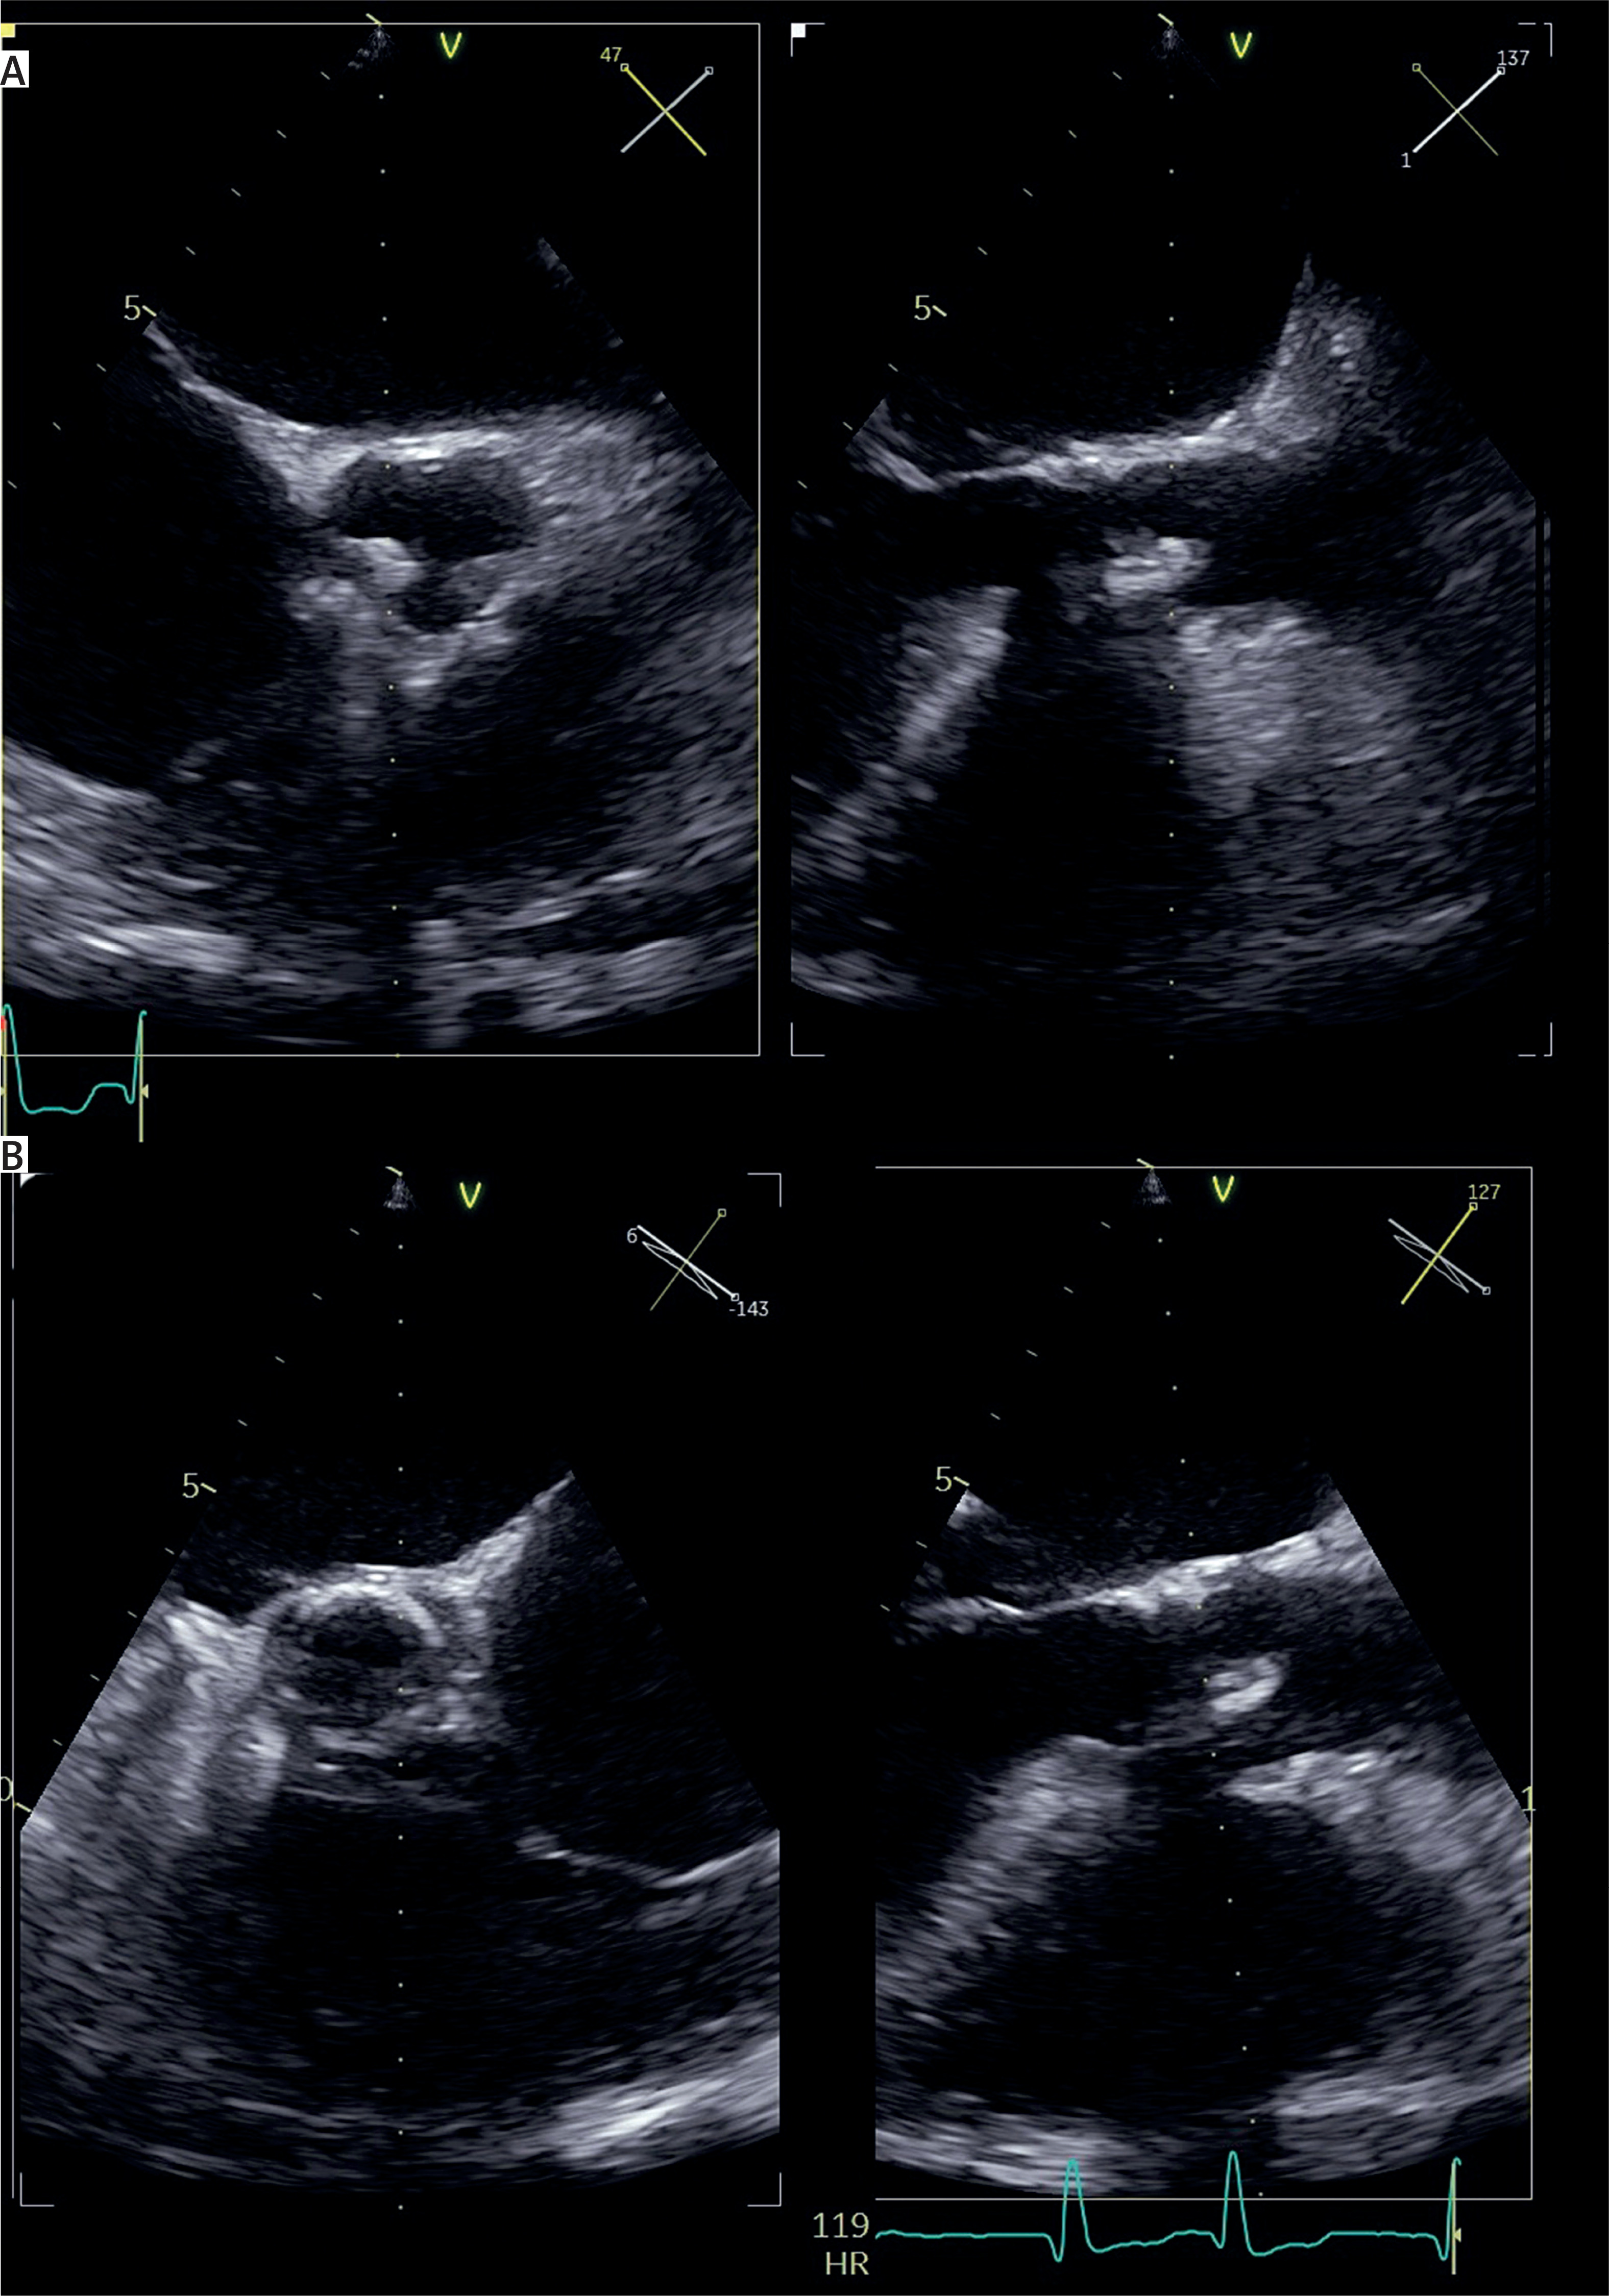

Figure 1

Transesophageal echocardiography. A – preoperative view of the biological prosthesis with visible vegetation. B – Postoperative view after valve-in-valve procedure with visible self-expandable valve

We present the case of a 79-year-old woman with endocarditis of a previously implanted prosthetic valve (Hancock II, 23 mm) who was multimorbid, including chronic kidney disease requiring dialysis, cirrhosis, hypertension, diabetes treated with insulin, and with a history of surgical aortic valve replacement 10 years before the onset of IE. She was admitted in critical condition to the Regional Specialist Hospital in Grudziądz, after the rapid development of heart failure, pulmonary edema, and severe aortic valve dysfunction on the 46th day of intensive antimicrobial treatment with a combination of vancomycin and ceftriaxone in the Department of Cardiology. A double-positive blood culture test confirmed IE, and vegetations were observed in transesophageal echocardiography (Figure 1 A). The patient was excluded from classical surgical aortic valve replacement because of the unacceptably high intraoperative mortality risk (EuroSCORE II = 96.57%). Due to the rapid deterioration of the clinical condition and the previously good condition during conservative treatment, the patient was deemed eligible for transcatheter aortic valve replacement. The procedure was performed via the femoral approach, and a Sapien 20 mm valve was implanted without complications. Postoperatively, a rapid improvement in the patient’s general condition and ejection fraction (from 15% preoperatively to 45% 1 day after the procedure) was observed, with no perivalvular leakage in postoperative transesophageal echocardiography (Figure 1 B). Blood culture tests performed 3 days after the procedure were negative. The symptoms of heart failure resolved postoperatively, and the patient was transferred to the Department of Cardiology for further treatment and discharged after 12 days. At 1-year follow-up, the patient was in an acceptable condition with no new symptoms and no perivalvular leakage. The patient’s written informed consent for publication of this case was obtained.